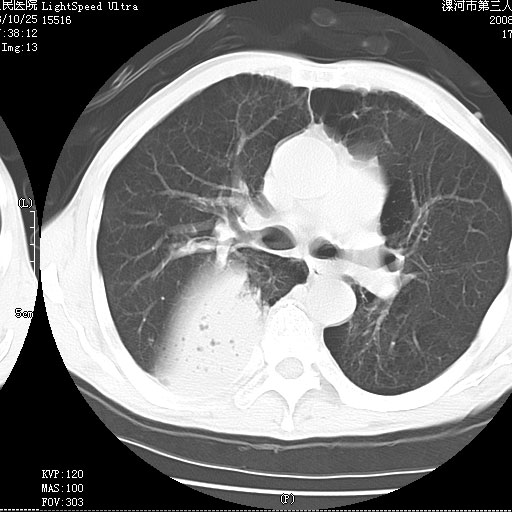

考虑为右肺下叶支气管痰栓形成并阻塞性肺不张及肺炎。

按肺叶分布,考虑肺不张

叶间裂前移,能考虑肺不张和肺栓塞吗?为什么不增强?大叶肺炎不能考虑吗?

右下肺阻塞性炎症,内见多发气体影,以肺叶分布.不支持不张.

右肺下叶肺脓肿,右肺下叶支气管痰栓形成。